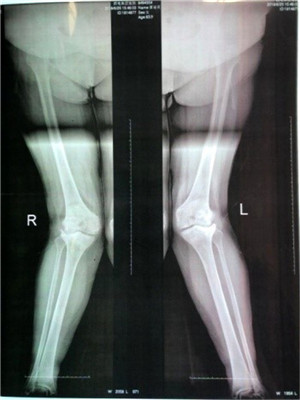

覃阿姨入院后,張主任認(rèn)真進(jìn)行了術(shù)前檢查,檢查結(jié)果為左下肢外翻29°,右下肢外翻31°。據(jù)張主任介紹,對(duì)于合并有膝外翻畸形的患者進(jìn)行人工膝關(guān)節(jié)置換術(shù)(TKA)的手術(shù)難度非常大,尤其是覃阿姨有一側(cè)腿屬于外翻角超過30°的重度膝外翻,這個(gè)手術(shù)極有挑戰(zhàn)性。為了提高手術(shù)成功率,降低手術(shù)風(fēng)險(xiǎn),骨科采用了目前最先進(jìn)的3D打印技術(shù)(即:利用特殊材料打印出與患者膝關(guān)節(jié)相同的模型)。經(jīng)檢查,張主任發(fā)現(xiàn)患者股骨外髁發(fā)育較小,脛骨平臺(tái)外側(cè)缺損較大,脛骨及股骨均外旋畸形。針對(duì)覃阿姨的情況,骨科立即進(jìn)行了模擬截骨手術(shù),對(duì)模擬手術(shù)遇到的問題現(xiàn)場(chǎng)討論解決,并制定了詳細(xì)的手術(shù)方案。經(jīng)過科室多次研究討論,張主任決定給覃阿姨實(shí)施雙膝關(guān)節(jié)置換手術(shù),應(yīng)用PS表面膝關(guān)節(jié)假體置換并備用限制性膝關(guān)節(jié)假體,通過手術(shù)來恢復(fù)患者雙下肢力線及功能。

膝關(guān)節(jié)置換術(shù)前術(shù)后對(duì)比